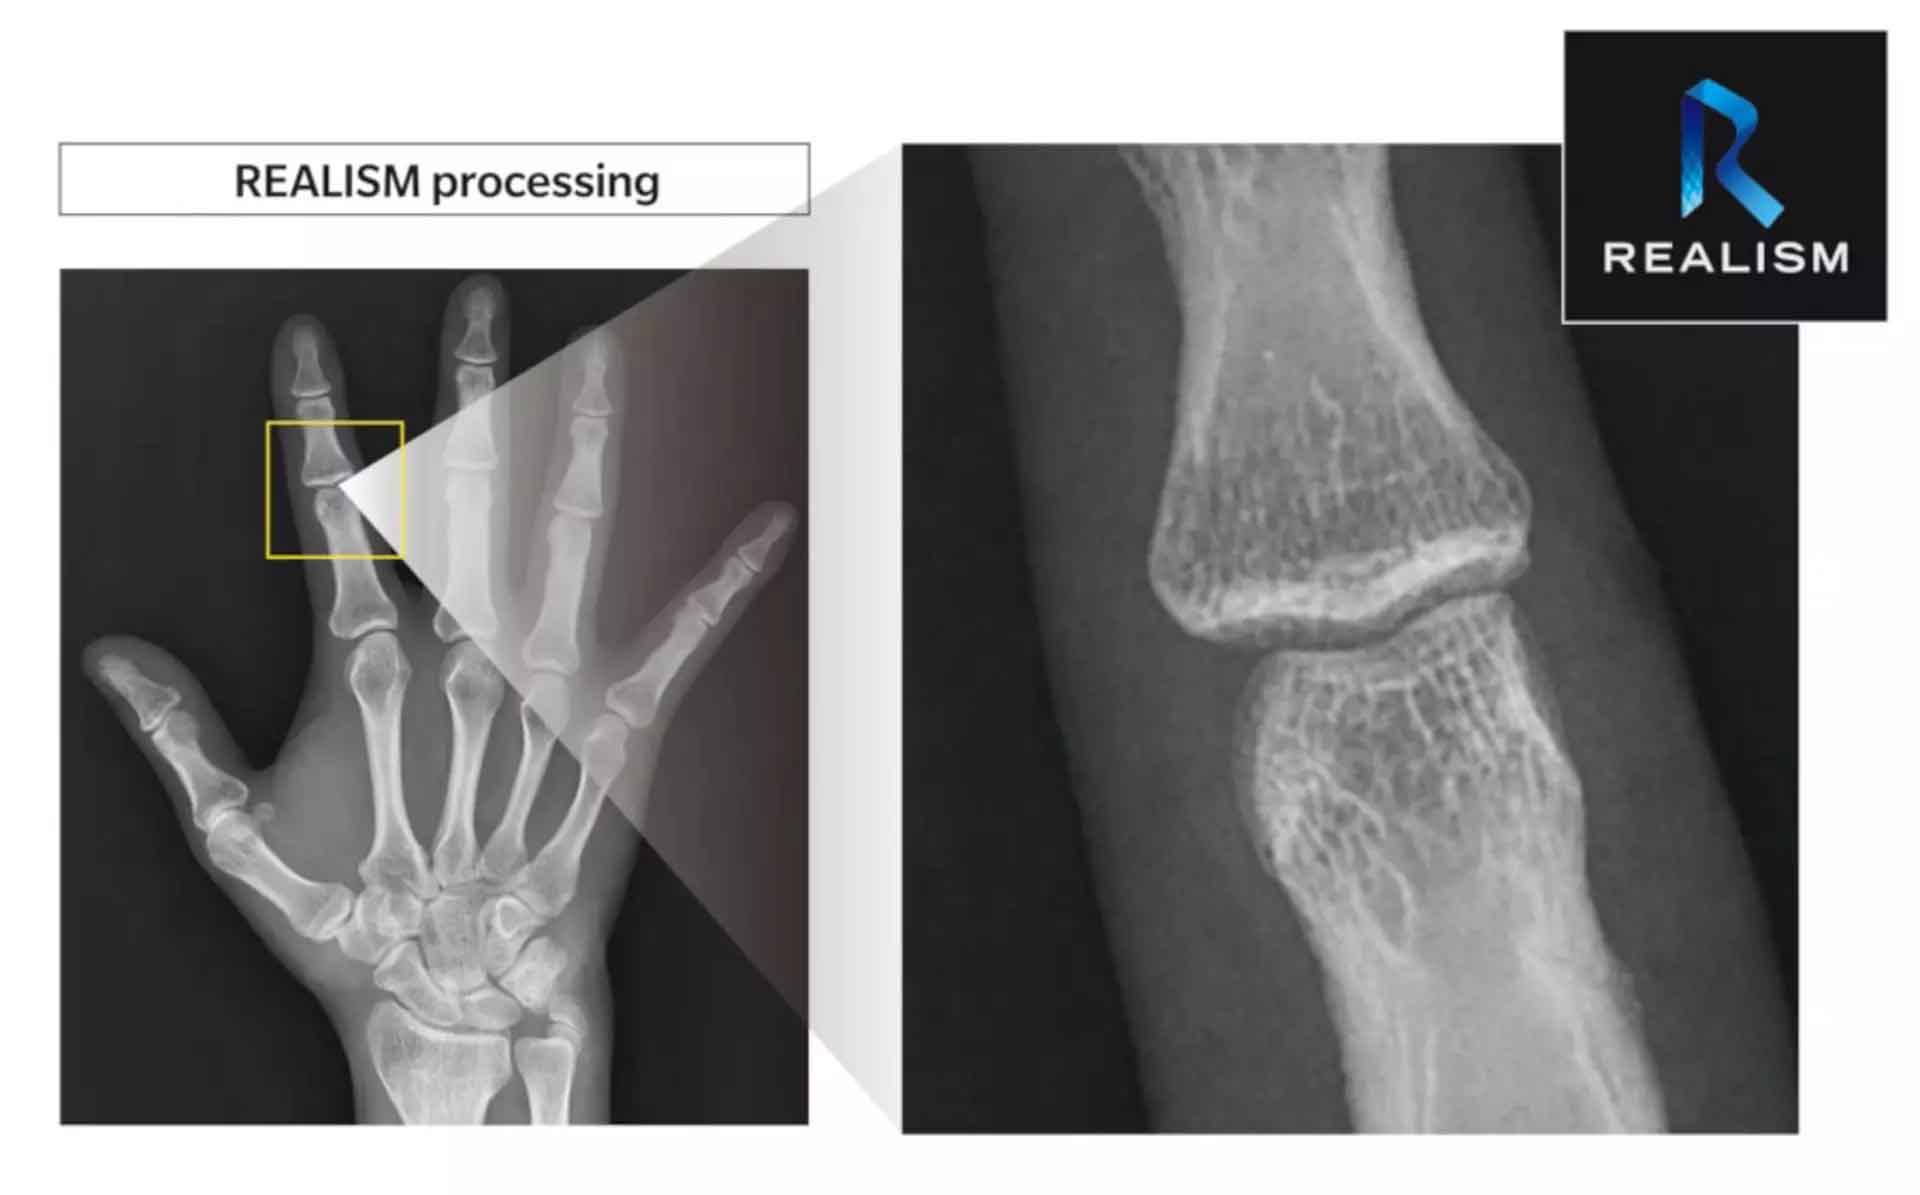

Alta qualidade de imagem – 150 micras

Processamento de imagem REALISM